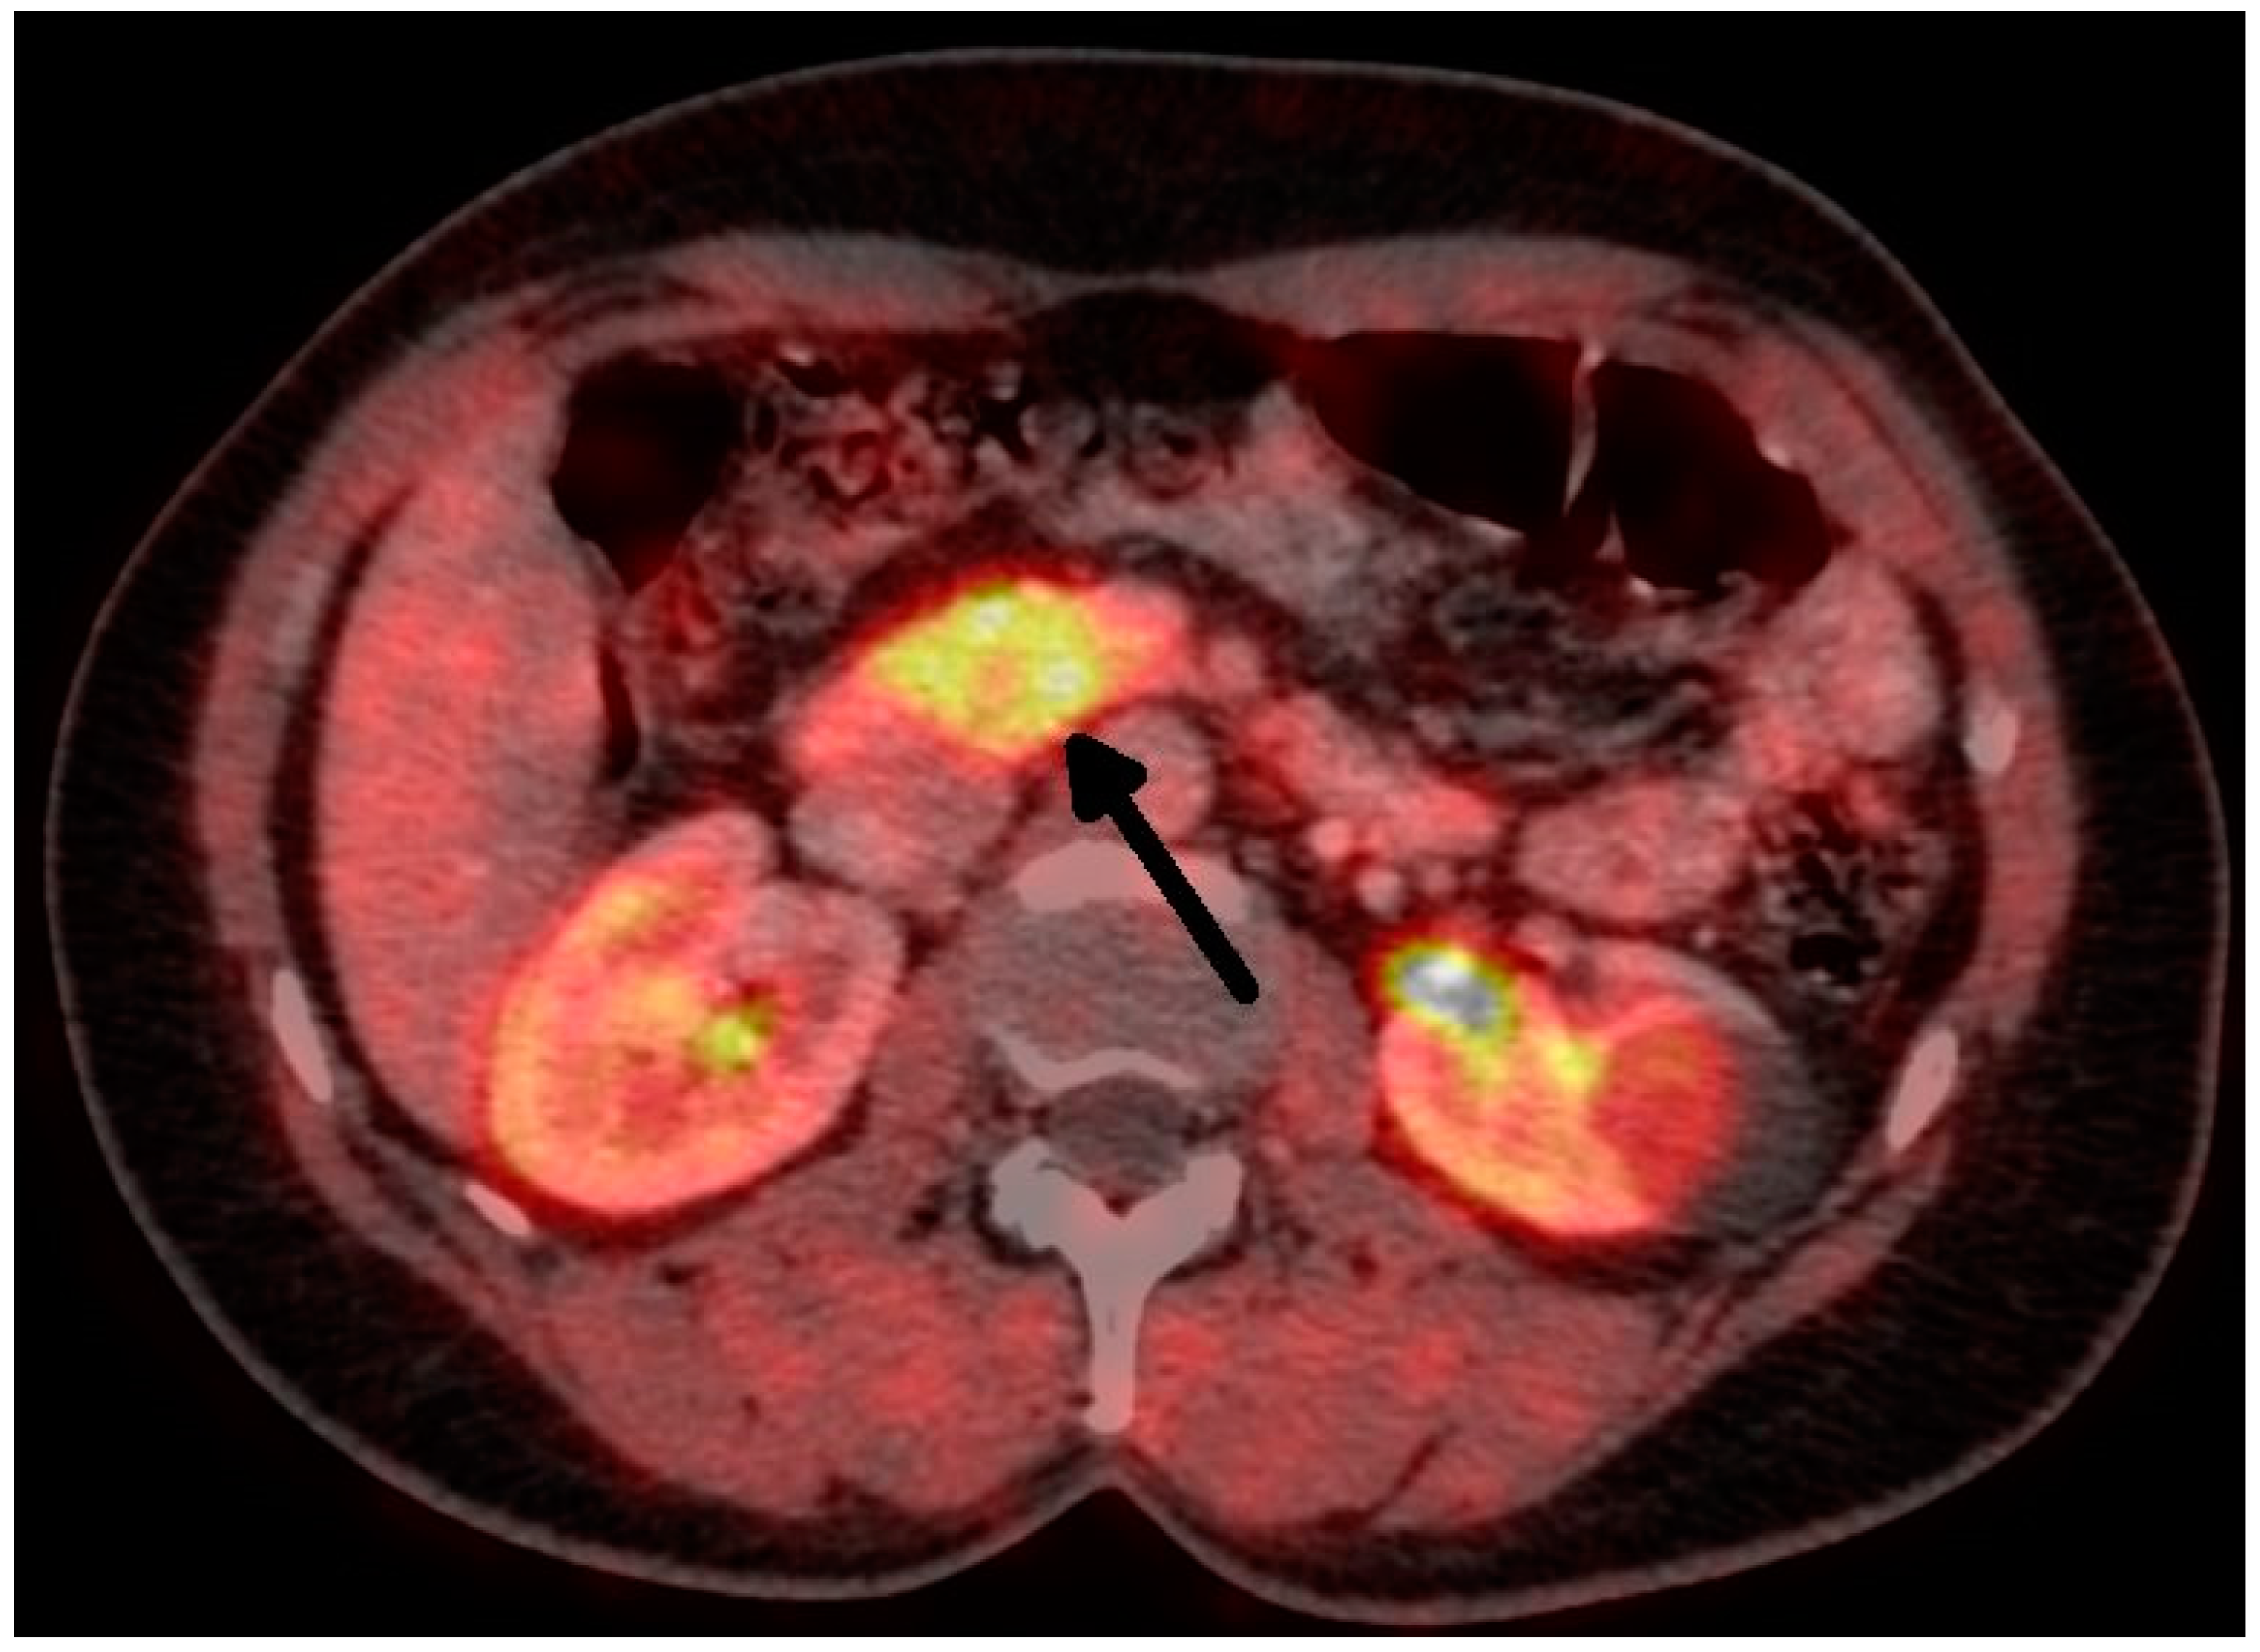

Figure 2.

Insulinoma—FDOPA PETCT (tumor marked with an arrow).

Overall, we performed a total of 116 scheduled surgeries on patients suffering from insulinoma. The surgically treated postoperative complications are listed separately. There were 79 females, with a mean age of 52 years (20–83 years, median was 51 years), and 37 males, with a mean age of 53 years (29–81 years, median was 59 years). The duration of the symptoms varied from 1 month to 25 years (mean was 3 years). All patients were examined in the 3rd Department of the Inner Medicine General University Hospital (which is focused on metabolic disease), including insulinoma localization. A fasting test was performed on all patients during hospitalization. Additionally, the levels of calcium and phosphates in the serum were examined in all patients, as well as in the hypophyseal region, to exclude MEN I syndrome. Radiological examination depends on the diagnosis period, and CT scan was used in all cases (Figure 1 and Figure 2). This was due to the unavailability of MRI, especially in the first years of the study.

The treatment of choice is surgery. Therefore, it is necessary to establish the precise localization of the tumor. The sensitivity and specificity of radiodiagnostic methods are rising. A conventional CT scan has a sensitivity of about 33%, while that of a single-slice helical CT is 58%, and that of multidetector CT is 75–100% [8]. Insulinomas are hypervascular, so they have greater enhancement during the arterial phase of the examination. The can be said of MRI. A conventional MRI can detect insulinoma in about 31% of cases, and multiphasic MRI can detect insulinoma in 85% of patients [4]. The use of 18 F-fluorodeoxyglucose (18 F-FDG) PET is not helpful in diagnosis due to the low proliferative activities of these tumors. Furthermore, 68 Ga-DOTApeptide PET is also not helpful, because it shows a low expression of SSTR subtype 2 [1]. The 68 Ga-DOTATATE scan is more sensitive for localization [1], but according to other studies, its sensitivity is lower than 20% [9]. Recent data show that 68Ga-DOTA-Exendin-4 PET/CT has better results, with a sensitivity of nearly 85% and a specificity of 100%. Exendin is a synthetic glucagon-like peptide-1, which is expressed in cases of insulinoma [10]. Unfortunately, we do not have personal experience with this method. Contrast ultrasound and endoscopic ultrasound are highly sensitive and specific (90–100%) [1]. All these methods are complementary, not competitive [4]. Despite the progress in diagnostic methods, in some cases, surgery can be indicated without precise knowledge as to the position of the tumor. An experienced surgeon can find the tumor in 42–95% of cases [1,5,11]. Moreover, there are some case reports about the intraoperative near-infrared imaging of insulinomas in the literature [12,13].